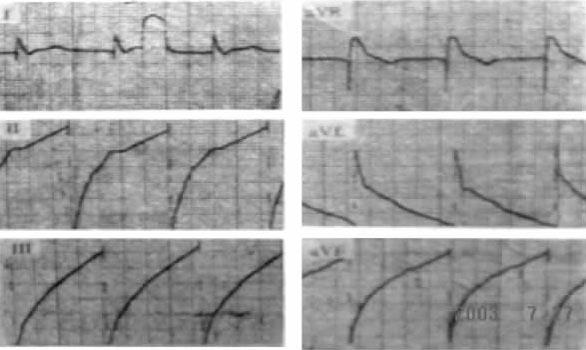

图7-1-3 右心室心尖部起搏心电图,起搏的QRS波呈LBBB+LAD,V5、V6导联QRS波主波向下

图7-1-4 右心室流出道起搏,起搏的QRS波呈LBBB,心电轴明显右偏

电极导线位于右心室流入道或流出道,起搏心电图亦呈LBBB型,但额面电轴不偏或显着右偏(图714)。如果患者原来的起搏心电图为右心室心尖部起搏图形,以后随访中出现额面电轴不偏或右偏,提示电极导线从右心室心尖部移位至右心室流入道或流出道。由于右心室流出道电极导线较难固定,通常在此部位起搏时,宜选用螺旋电极导线。有报道右心室流出道起搏与右心室心尖部起搏相比,心排血量提高了90%,证明右心室流出道起搏对血流动力学改善更具帮助。罕见的情况下,即使电极导线顶端位于右心室流出道,心电图仍呈右束支阻滞图形。可能机制包括:① 选择性起搏右束支,刺激经右束支快速逆向传至希氏束和左束支,使左心室较右心室提前激动;② 患者本身存在右室激动的延迟,从而左心室的激动早于右心室;③ 左右束支之间存在“短路”,起搏冲动自右向左快速传递,从而提前激动左心室。

偶见原来右心室心尖部起搏的患者,转为左心室起搏,起搏心电图变为完全性右束支阻滞图形(图715),可能的原因包括:① 右心室前壁穿孔,电极导线的顶端穿入心包腔,位于左心室外膜,起搏冲动夺获左心室;② 导线穿过室间隔进入左心室;③ 电极导线脱位,滑入冠状静脉系统左室分支,起搏夺获左心室;④ 罕见的情况尚有在安装起搏器时,导线循经未闭卵圆孔或房间隔缺损直接进入左心系统,此时,侧位透视有助于鉴别导线位置。

图7-1-5 左心室起搏,起搏的QRS波呈RBBB图形